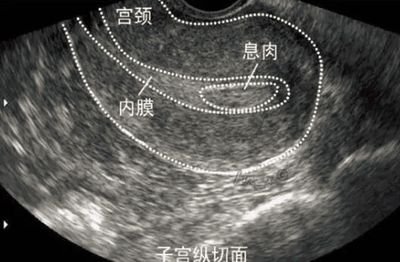

首先,我們需要了解胚胎著床是如何發(fā)生的。在受精后的第5至7天,胚胎會(huì)從輸卵管進(jìn)入子宮腔,并開(kāi)始尋找合適的著床位置。這個(gè)過(guò)程依賴于胚胎自身的發(fā)育潛能、子宮內(nèi)膜的容受性以及母體激素水平的協(xié)調(diào)。一旦胚胎成功附著于子宮內(nèi)膜,便會(huì)逐漸植入并建立血液循環(huán),標(biāo)志著妊娠的正式開(kāi)始。